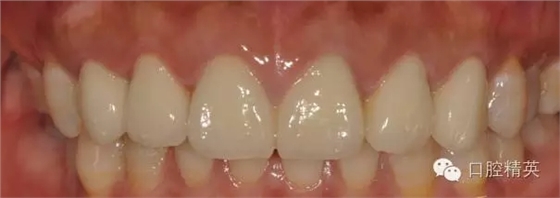

修復體完成后正面觀